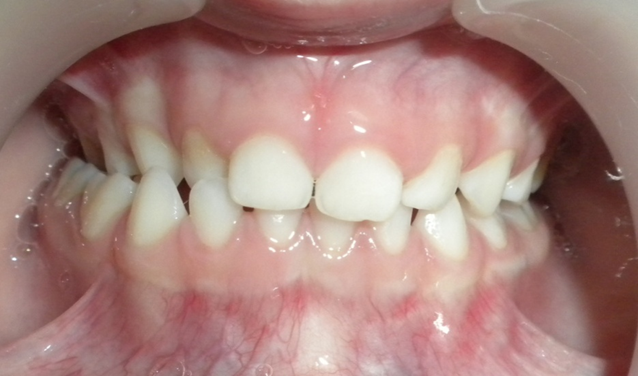

Image : Orthodontie pédiatrique Archives – ODF

Exoalvéolie Mandibulaire

Définition

Anomalie moins fréquente, caractérisée par :

- Une mandibule trop large, la rendant visible sur la face.

- Une langue volumineuse, trop basse et antérieure.

- Une vestibuloclusion des dents inférieures.